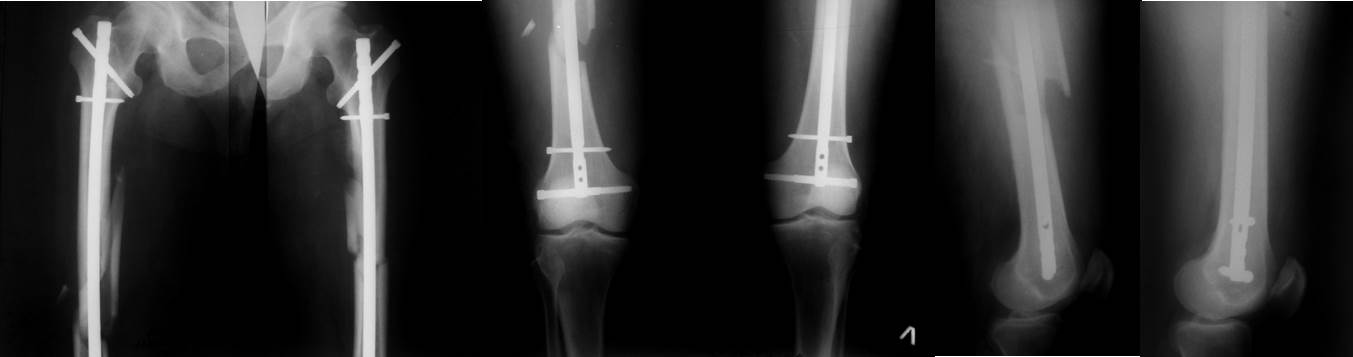

Уважаемые коллеги, приношу тысячу извинений за некачественныe Р-снимки, снятые передвижным Р-аппаратом, рентген отд находиться метров 300 от нас, попозже будут качественные снимки. Клинически укорочения, ротации не определяется, ось бедра правильная, только рентгенологически отмечается небольшой вальгус, т.к без ЭОП применение поллерных спиц или винтов невозможно, конечно, надо было при помощи слоников дистально блокировать и в сагиттальной плоскости.

Чтобы ответить на вопрос «оставлять как есть или переделывать», необходимо знать какой философии остеосинтеза придерживается лечащий врач. Если «может быть и срастётся», то результат остеосинтеза допустимый. Если ставится цель получать гарантированные воспроизводимые результаты для каждого оперированного перелома в виде сращения и отсутствия деформаций, то такой остеосинтез нельзя признать приемлемым. Четыре причины, по которым, с моей точки зрения, «так оставлять нельзя»:

1. Деформация. Вальгусная деформация в месте перелома 12 градусов. Как её расценивать у двадцатидвухлетнего пациента: как допустимую или нет? Сложный вопрос. Но это только часть проблемы. Вальгусная деформация в послеоперационном периоде может увеличиться на 6-7 градусов, поскольку перелом ниже истмуса и диаметр костномозгового канала на входе дистального отломка намного больше диаметра стержня. Поэтому начинает играть роль разность в диаметрах блокирующих винтов (3,5 мм без резьбы) и отверстий для блокирования в стержне (4,5 мм). Из-за этой разницы возникает нестабильность дистального отломка во фронтальной плоскости с общим объёмом движений «варус-вальгус» в 12-14 градусов. Это легко доказать математически. Я думаю, что доктор определит его и клинически, придавая дистальному отделу конечности варусное или вальгусное положение. Поэтому в послеоперационном периоде можно ожидать вальгусную деформацию до 20 градусов, что является, с моей точки зрения, неприемлемым результатом лечения для специализированного отделения.

2. Стабильность. По вышеперечисленной причине отсутствует и стабильность между отломками, что ставит под угрозу конечный результат лечения – сращение перелома.

3. Нагрузка. Трудно рекомендовать больному хоть какую-то нагрузку при таком остеосинтезе. Нагрузку на дистальном конце стержня несёт только один винт в круглом отверстии с диаметром без резьбы 3,5 мм, что крайне недостаточно. Второй винт проведен некорректно, по нижнему краю овального отверстия. Для нагрузки он потерян. Если он вводился таким образом намеренно, для выполнения в последующем динамизации, то динамизация при таком переломе вообще противопоказана. Хотелось бы видеть и проксимальное блокирование. Таким образом, выпадает очень важный элемент в лечении блокированным остеосинтезом – нагрузка.

4. Судя по количеству отверстий в кости – дистальное блокирование далось нелегко. Прочность кости в этом месте снижена. В процессе реабилитации этот участок кости находится под угрозой и нельзя исключить перелома на уровне дистальных блокирующих винтов. Поэтому напрашивается остеосинтез более длинным стержнем с дистальным блокированием в мыщелках бедренной кости. Мы предпочитаем вводить стержень на всю длину кости и блокирование выполнять в мыщелках бедра.

Есть ещё несколько причин, по которым «так оставлять нельзя», но пост получается слишком длинным. Не в качестве пиара, а только для пользы дела - пример из личной практики трёхнедельной давности.

Переломы обоих бёдер фиксированы стержнями той же фирмы, что и в обсуждаемом случае. Остеосинтез обоих бёдер выполнен за одну операцию продолжительностью 2 часа 40 минут. Положение больного на боку на обычном хирургическом столе. Репозиция отломков в «custom-made» спицевом репозиционном аппарате на двух спицах с корректором угловых деформаций. Определение точки ввода и проведение спицы, как правило, с первой попытки с помощью «custom-made» прицельного устройства. Рентгеновский снимок только для подтверждения расположения спицы. Ни на одном этапе операции режим прямой флюроскопии не используется. Введение стержня на уже репонированном переломе. Самое дистальное отверстие в стержне предварительно до операции рассверлено до диаметра 6,55 мм и при дистальном блокировании в него вводится по предварительно проведенной спице канюлированный блокирующий винт диаметром 6,5 мм той же фирмы. Введением такого винта решается сразу три задачи. Во-первых, исключается «шат» во фронтальной плоскости, поскольку разница между диаметром отверстия и диаметром винта всего 0,05 мм и во-вторых, отпадает необходимость во введении винта в сагитальной плоскости, и в-третьих, он способен без проблем держать нагрузку при ходьбе. Дистальное блокирование с помощью «custom-made» механического прицельного устройства, не требующего не только режима прямой флюроскопии, но и вообще рентгенологического подтверждения попадания блокирующих винтов, что значительно сокращает время вмешательства. Соответствующее дистальному и проксимальное блокирование, чтобы обеспечить больному сразу полную нагрузку на ноги. Вертикализация больного на пятые сутки после операции, контрольная рентгенограмма, которую вы видите, на двенадцатые сутки перед выпиской. Больной был уже неделю на ногах. Понимаю, что у каждого доктора свой опыт и предпочтения в выполнении блокированного остеосинтеза и свои представления о нём. Мы пользуемся именно такой методикой и техникой, к которым мы шли более десяти лет и которая на протяжении десятков операций даёт предсказуемые результаты лечения в виде отсутствие деформаций и несращений. Но, как известно, на вкус и на цвет товарищей нет. Правда у каждого своя.